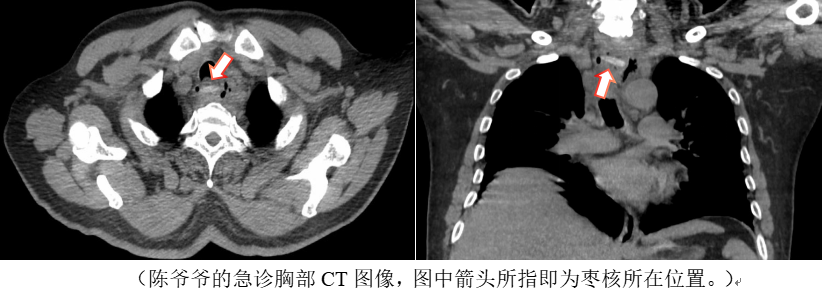

2024年1月,天气依然寒冷,笔者又遇到一位因体温持续升高不降而就诊于发热门诊的75岁陈爷爷,时值呼吸道疾病的高发季节,内科医生以评判是否存在肺部炎症为陈爷爷开具了胸部CT。CT图像中陈爷爷的双肺并没有看到活动性的炎症,但是在食管上段却发现一枚横行条状异物已刺穿食管壁,导致食管管壁增厚水肿,并引发纵隔感染。追溯病史,陈爷爷的子女回忆起家里近几日确实做过含红枣的食物。情况危急,经过内外科的协同治疗,陈爷爷的病情才得到控制。